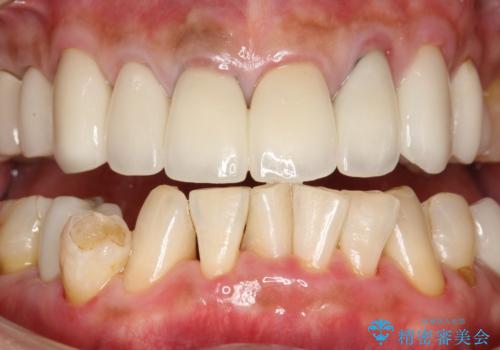

- 約1年ぶりの来院のため、着色や歯石がかなりついてしまっため、綺麗にしてほしいとのことでした。PMTC30分コースを行いました。

PMTC(保険外治療)は、毎日の歯磨きで落としきれない汚れや、コーヒ、紅茶などによる着色・タバコのヤニなどの着色も除去します。目には見えない歯と歯の間・歯肉の境目などに残っているプラーク(歯垢)もしっかり取り除きます。PMTCでは専門的な機械や材料を使用して、徹底的に汚れを除去するため、虫歯・歯周病・口臭予防などにつながります。